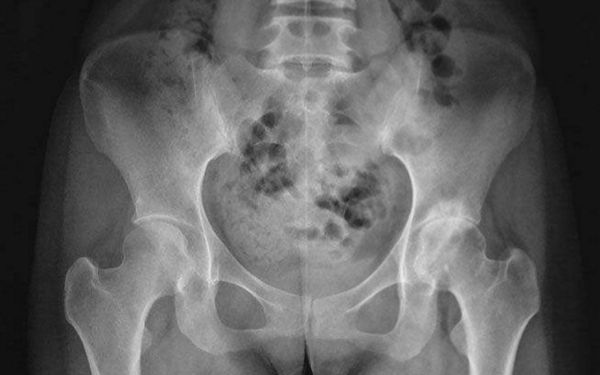

16/12/2021 21:12Cô gái trẻ đau lưng không ngủ được, chụp thấy xương 'thủng như tổ ong', tất cả do 1 loại nước nhiều người mê

Nửa tiếng sau, Phi Phi đã nằm trên giường bệnh, bác sĩ tiêm một ít thuốc giảm đau cho cô để giảm đau tạm thời, sau khi kiểm tra, Phi Phi bị loãng xương, xương rất dễ gãy, khiến hông cô bị đau do xương bị lệch.

Bác sĩ nói với Phi Phi rằng mật độ xương của cô ấy rất thấp và xương của cô ấy trông giống như "tổ ong", nhưng điều này khiến cô đầy nghi ngờ, cô ấy mới 28 tuổi, làm sao xương có thể trở nên như thế này?

Bác sĩ nói trà sữa rất nhiều calo, uống lâu sẽ ảnh hưởng đến quá trình trao đổi chất của cơ thể, từ đó ức chế quá trình hình thành xương và làm chậm quá trình phát triển xương. Hơn nữa, trà sữa chứa nhiều kem béo và đường, uống quá nhiều sẽ ảnh hưởng đến sự hấp thụ canxi, làm giảm hoạt động của các nguyên bào xương trong quá trình chuyển hóa xương, dẫn đến giảm mật độ xương, lâu dần sẽ dẫn đến loãng xương.